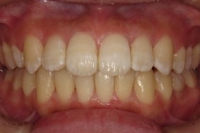

CASE2

↓前歯の歯並びを きれいに治したい。

(35歳/女性)

|||||||||

概要・担当医コメント:叢生・審美障害↑

動的治療期間13ヶ月(12回)/非抜歯/費用概算:55万円

上は固定式のブラケット矯正で,下は患者様ご自身が着脱するマウスピース矯正の治療を行いました.治療結果には大変満足されているそうです.